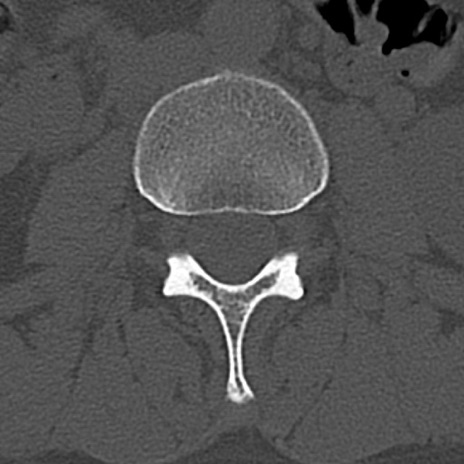

腰椎CT

横断像と矢状断像